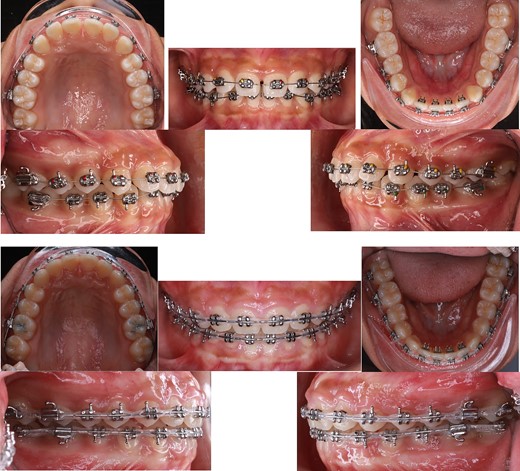

During the initial stage, orthodontic treatment was utilized to close the gaps between the teeth and move the upper and lower front teeth back using a fixed appliance, reverse curve wire, and power chain to achieve control tipping movement and improve her convex profile [6]. Tongue spurs were attached to keep the tongue in the correct position and prevent gaps from forming between the teeth. At the same time, a wire was used to intrude the upper front teeth during orthodontic treatment. The 3D simulation [7] before the treatment was done for consulting with patient and patient’s family (Fig. 2). The following procedures were performed: a fixed appliance was attached to both the upper and lower arches. Over a period of 4 months, alignment and levelling were done using a Niti wire, followed using a stainless-steel wire to close all the spaces using a sliding mechanic with reverse curve stainless steel wire bending on 0.017 × 0.025 SS and power chain. In the final 3 months, the detailing and finishing stage were completed to achieve functional occlusion (Fig. 3).

Tongue spurs bonding, alignment, leveling and space closure phase of the treatment.